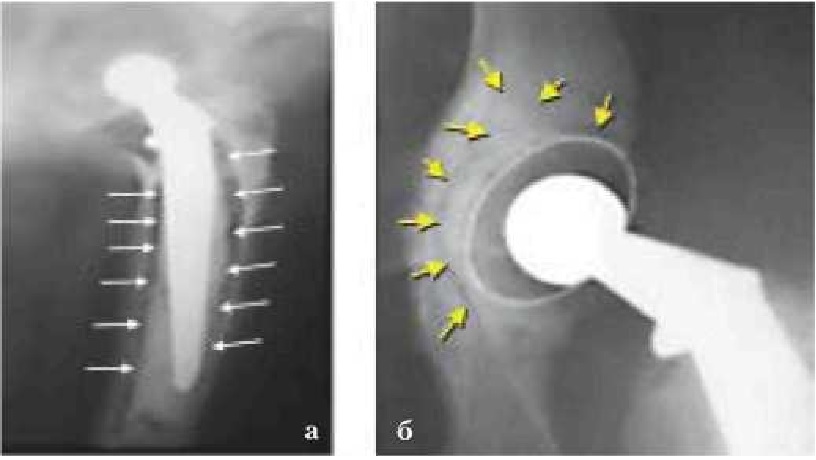

При данном осложнении прибегали к ревизионному эндопротезированию с дополнительной расточкой суставной впадины и последующей фиксацией чашки. В двух случаях выполнена костная пластика дорсального и краниолатерального края суставной впадины, а в одном эндопротез пришлось удалить. АН обоих компонентов эндопротеза наблюдали в 6 из 15 случаев (40 %) (рис. 2), причем у одного животного — двустороннюю в разные промежутки времени.

Рис. 2. Рентгенограмма. Асептическая нестабильность бедренного (а) (ножки) и вертлужного (б) компонента (чашки) эндопротеза. Стрелками показано разрушение костной ткани (остеолиз)

Во второй группе животных средний срок службы ЭП составил 1569 сут (от 798 до 2127) (рис. 3). АН развилась в 2 из 18 случаев (11,1 %). Появление хромоты и зоны лизиса костной ткани вокруг цементной мантии ЭП отмечали в среднем через 520 сут (336 и 704). Этим животным операция была выполнена повторно.